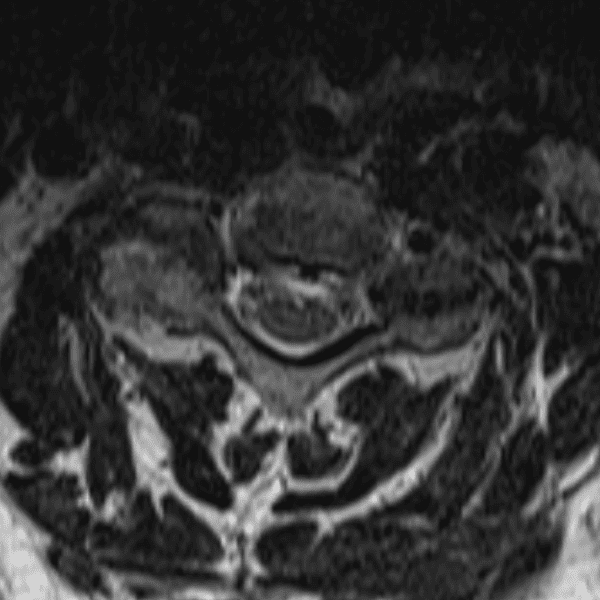

Simulates call by including subtle or difficult cases and some normals.

35 cases